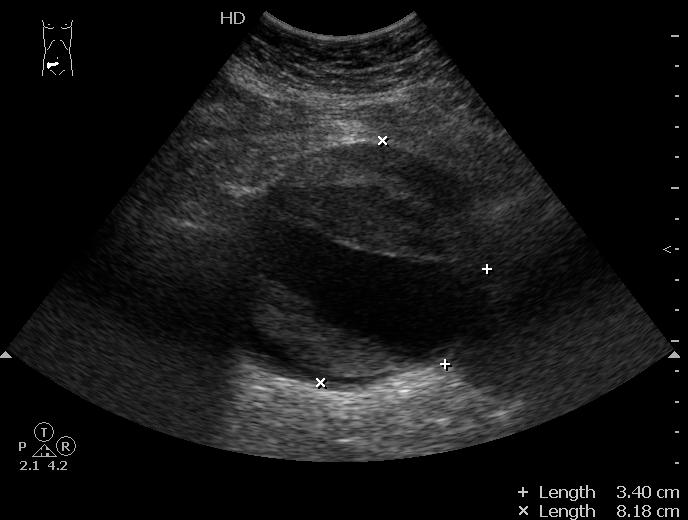

Разрыв аневризмы брюшного отдела аорты

Да, сегодня пришел своими ножками на контрольное исследование.

Ему выполнена резекция аневризмы, установлен "Y"-протез.